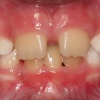

Diasteem

Diasteem – vahe esimeste hammaste vahel. Esineb 50%-l 6-8 aastastel lastel. Kuni 2 mm diasteemi puhul on, peale lateraalse intsisiivi ja silmahamba lõikumist, võimalik diasteemi iseeneslik sulgumine. Diasteem, mille suurus...